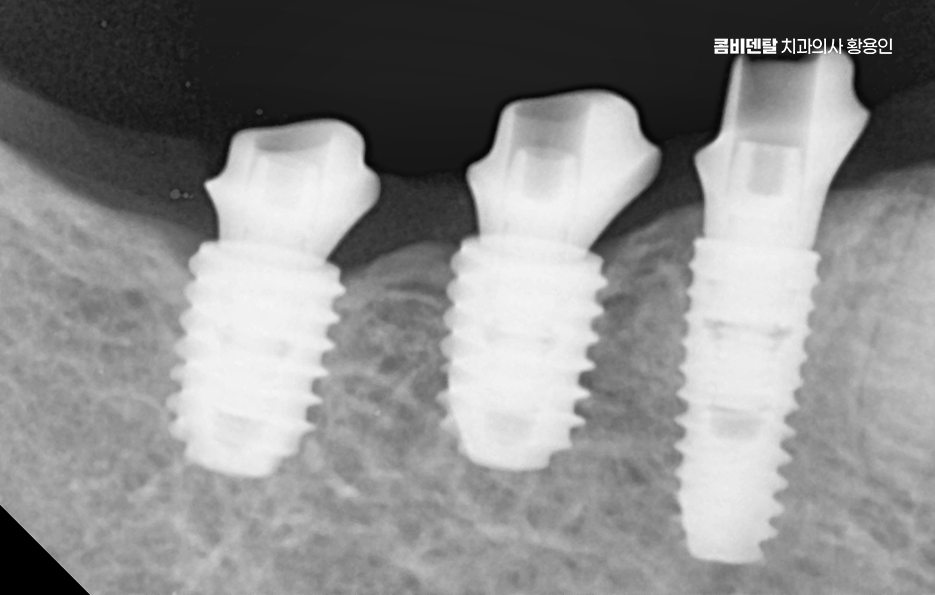

이러한 문제를 막기 위한 효과적인 방법이 바로 임플란트 치료로 어금니 임플란트를 계획할 때는 먼저 잇몸뼈 상태를 정밀하게 확인해야 하며 3D CT 촬영을 통해 뼈의 높이와 두께, 그리고 임플란트를 심을 수 있는 공간을 세밀하게 분석해야 하며 위턱 어금니 같은 경우 상악동이라는 빈 공간이 바로 위에 있어서, 치아가 빠지고 나면 그 공간이 아래로 내려와 임플란트를 심을 자리가 부족해지는 경우가 많고 아래턱 어금니는 하치조신경이라는 중요한 신경이 지나가기 때문에, 신경을 피해서 정확한 위치와 각도로 식립하는 계획이 필요할 수 있어요

어금니는 심미성보다는 저작력을 우선하기 때문에 내구성이 높은 구조로 설계하게 되며 치료가 끝났다고 해서 끝이 아니라, 정기적인 유지관리와 스케일링, 임플란트 주위염 예방을 위한 위생 습관이 반드시 동반돼야 하고 특히 어금니는 입 안 깊숙한 곳에 위치하기 때문에 칫솔질이 어렵고, 음식물이 잘 끼기 때문에 워터픽이나 치간칫솔을 병행해서 관리하는 것이 장기적인 치료 성공과 유지에 있어서 관건이라 할 수 있었어요

결론적으로 어금니 임플란트를 하지 않고 방치하면, 단순히 어금니 하나의 문제가 아니라 전체 교합, 반대편 치아, 나아가 턱관절 기능과 소화 건강까지 영향을 주게 되기 때문에, 가능한 빠르게 치료를 결정하는 것이 장기적으로 더 많은 비용과 시간을 절약하는 방법이 되는 거예요. 특히 뼈가 아직 충분하고, 주변 치아가 건강할 때 임플란트를 진행하면 예후도 좋고, 추가적인 뼈이식이나 부가 수술 없이도 비교적 간단하게 치료가 가능한 경우가 많아서 어금니 상실 후에는 임플란트 치료와의 연계를 잘 고려해서 치료 계획을 늦지 않게 세우시길 바라고 있어요